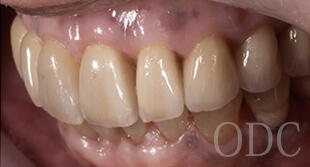

オールオンフォーの症例

"見える部分"は、デンタルテクニシャンの技術で決まります。

インプラント治療で、もっとも高い技術力が必要とされるうちの1つが全顎的な症例です。噛み合わせを熟知していなければ顎関節に支障をきたし補綴物の永続性は保てないのです。そしてオーキッド歯科クリニックのインプラント治療を支えるデンタルテクニシャン(歯科技工士)の技術も重要です。

術 前

初診時87歳、男性。上顎は歯周病により残存歯を長期的に機能させることが困難と判断し、全て抜歯。出来る限り早期の咬合機能の回復と審美性の実現が求められ、上顎は「4本のインプラントで失った全ての歯を固定し、手術当日から噛む機能を回復させることが可能」なオールオン4という術式を選択。オールオン4は「治療期間」「経済性」「審美性」「外科的侵襲」などのあらゆる負担を軽減した全く新しいコンセプトの画期的なインプラント治療です。 下顎の欠損部位に対しても、術前の診査診断をしっかり行い合計5本のインプラントを埋入しました。

インプラント治療を成功に導く為に必要不可欠な歯科技工。インプラント補綴は、特に技工士の技術が重要となる。オールオン4において、“口の中の見える部分”は全て歯科技工士の仕事なのです。当医院のオールオン4補綴はインプラント補綴で有名なノーベルバイオケア社公認インストラクター 志田和浩氏によるものです。本症例は、1歯1歯プロセラを装着した、オールオン4の上部構造としては最高級のものの一つです。